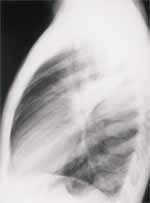

En otras oportunidades las infecciones vírales pueden presentarse con un patrón menos común caracterizado por infiltrado retículo nodular difuso, que ocasiona velamiento completo en la transparencia de uno o ambos pulmones (Figura 6), este último patrón es más común en los cuadros de neumonitis intersticial descamativa. Además, los defectos fagocitarios, pueden presentarse en la radiografía de tórax como consolidaciones pulmonares16.

FIGURA 6. Paciente lactante menor con cuadro de infección respiratoria viral, manifestado por infiltrado reticular

difuso con velamiento en la trasparencia de ambos parénquimas pulmonares.